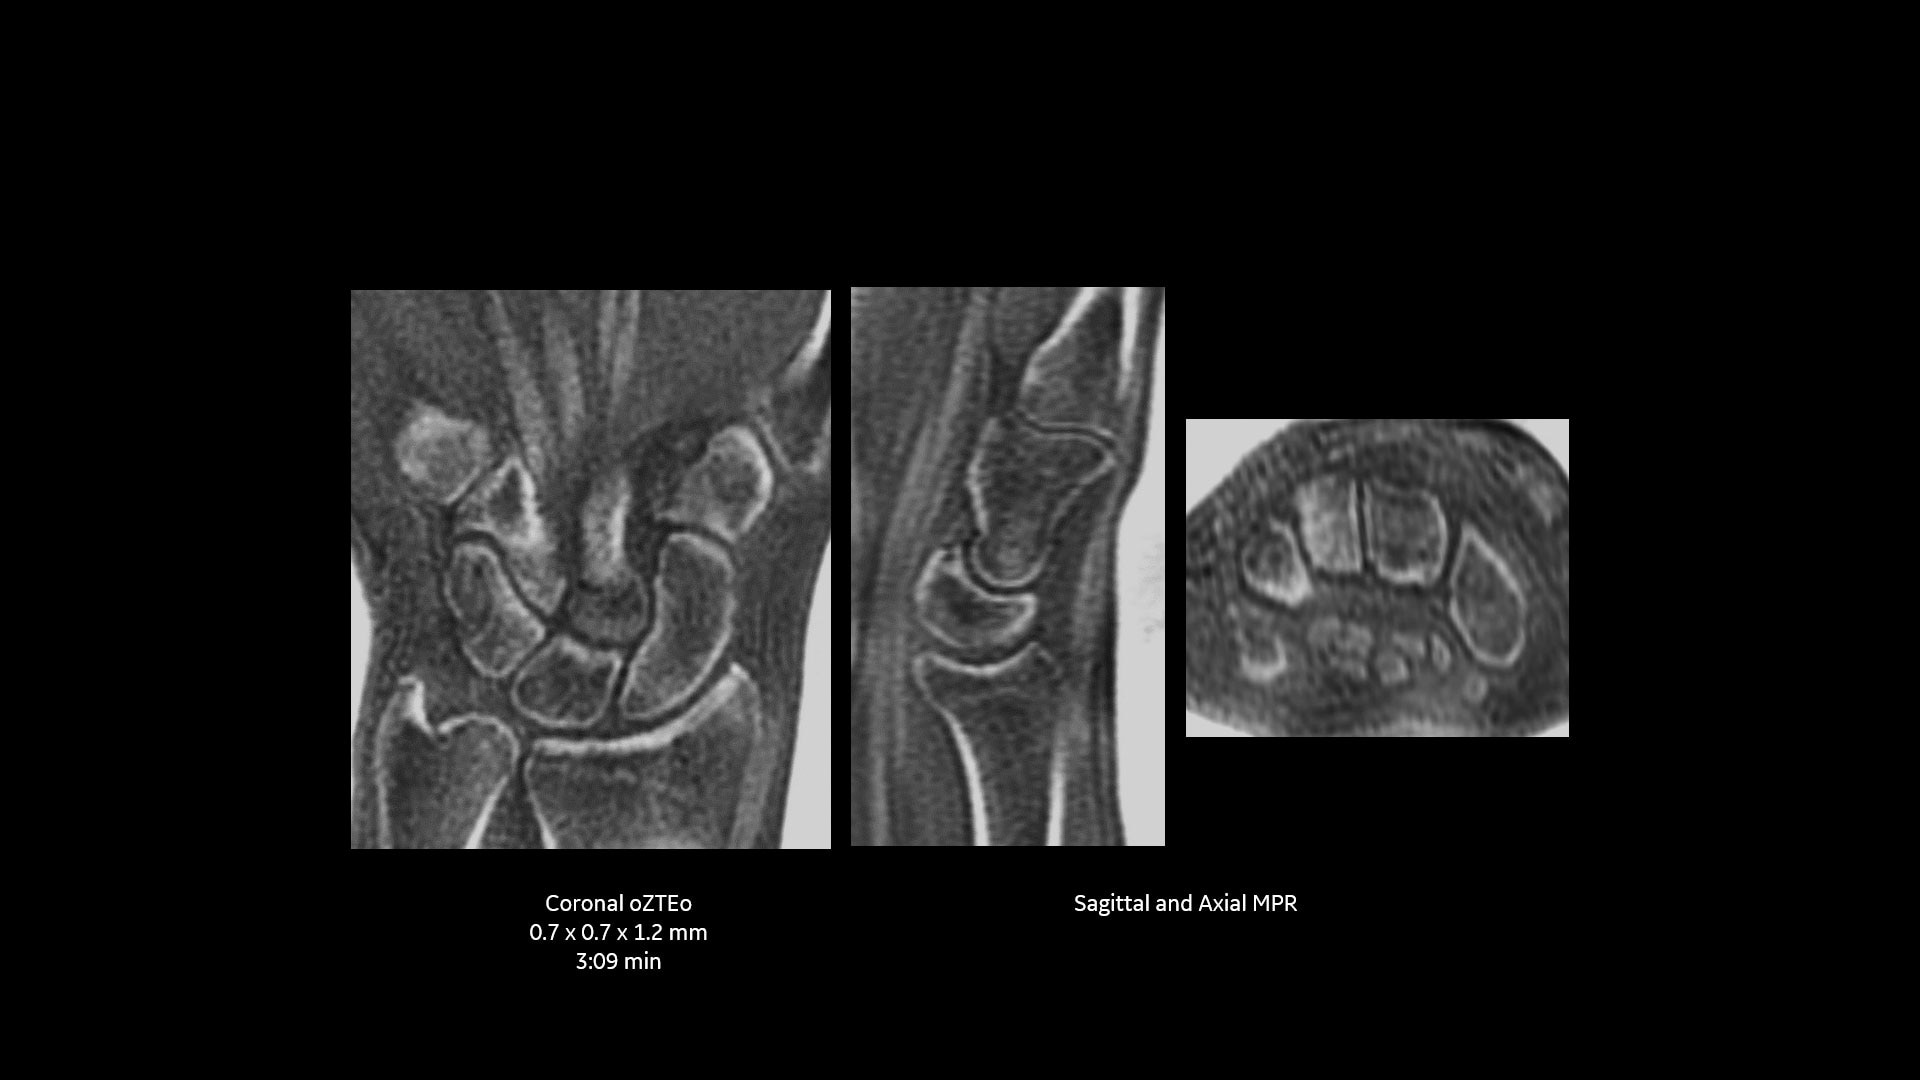

oZTEo ist für alle Anatomien ohne ionisierende Strahlung verfügbar und liefert dabei Bilder von Knochenmorphologie, Verkalkungen, Verknöcherungen und Frakturen. OZTEo ergänzt die herkömmliche MRT-Weichteilgewebeuntersuchung mit perfekter Anpassung und bietet isotropische 3D-Bildgebung unter Verwendung einer radialen ZTE-Erfassung (Zero TE) mit inhärenter Unempfindlichkeit bei Bewegungen. Verwendung von oZTEo mit Volumenbeleuchtung für realistisches 3D-Rendering.

Wenn oZTEo in eine MRT-Untersuchung einbezogen wird, werden Kortikalisknochendaten perfekt zusammen mit den Weichteilgewebsserien registriert, was sie zu einer zentralen Bildgebungsserie für die meisten routinemäßigen MSK-Anforderungen macht.

Mit dieser neuen Anwendung zur Darstellung von kortikalen Knochenoberflächen, basierend auf der radialen ZTE-Anwendung, können Sie eine neue Möglichkeit für die Knochenbildgebung anbieten und einen erheblichen klinischen Nutzen für Ihre orthopädischen Untersuchungen gewinnen.